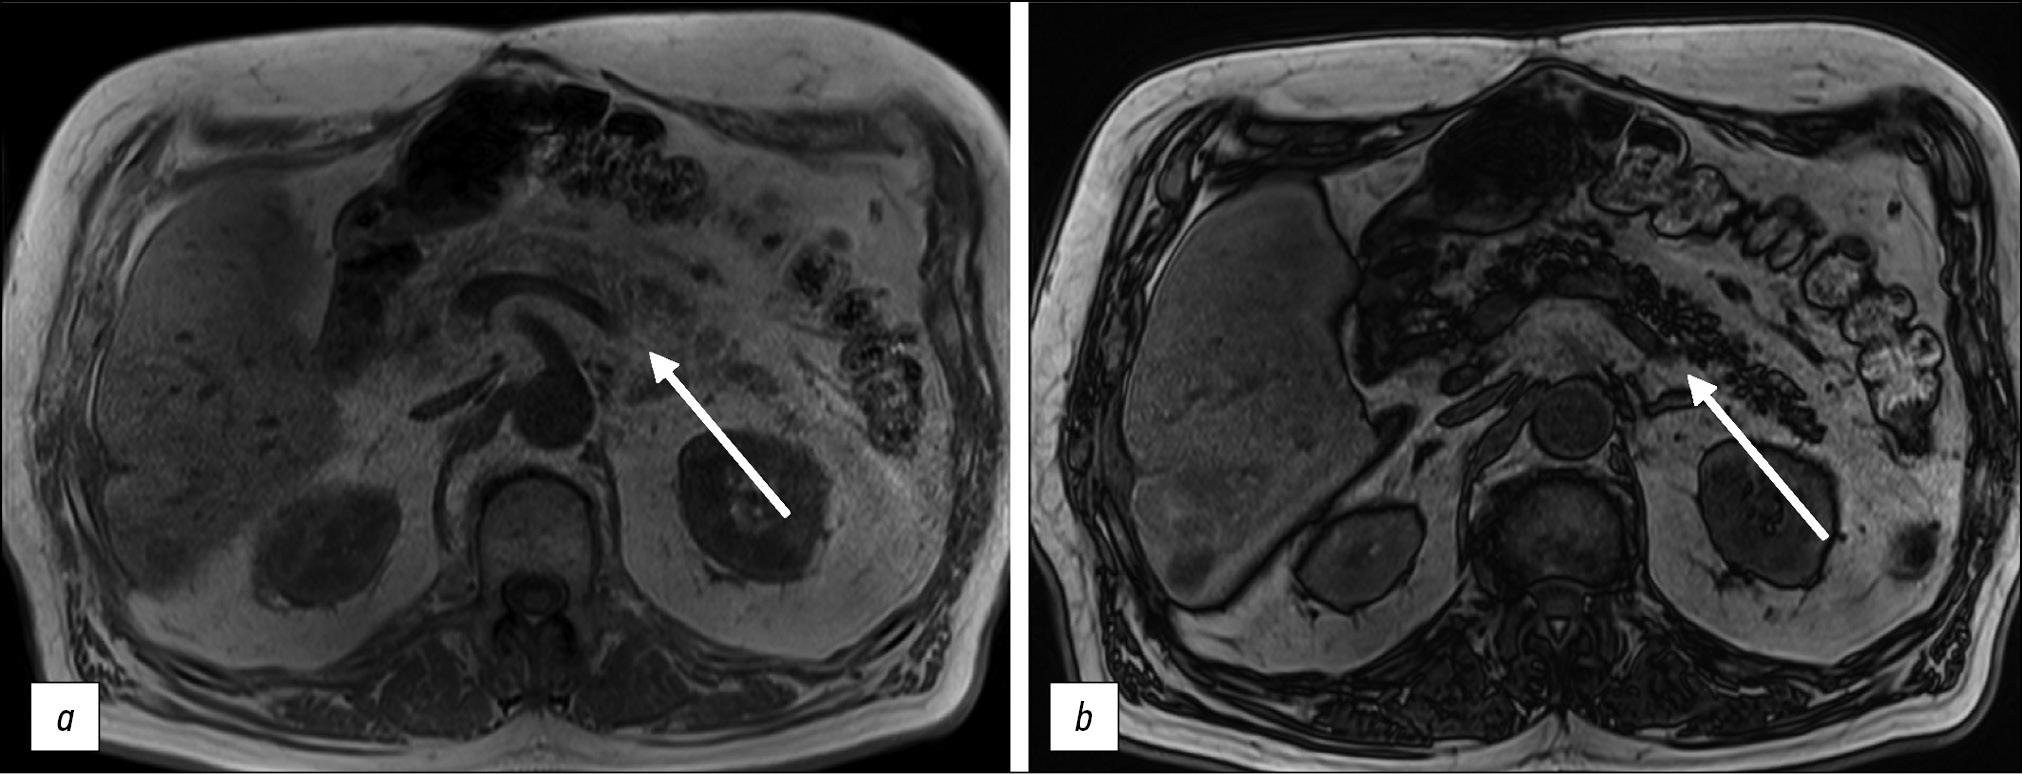

For a more accurate assessment of hepatic steatosis or signs of hemochromatosis, in-phase and opposed-phase T1-WIs should also be included in the standard MRI protocol. Furthermore, this sequence is useful in the diagnosis of adrenal adenoma (Fig. 6), clear-cell renal cell carcinoma, and pancreatic fatty infiltration (Fig. 7). These sequences must be obtained before contrast agent injection. Out-of-phase images allow for the assessment of signal loss from adipose tissue and fat-containing lesions such as liver adenomas or hepatocellular carcinoma. Moreover, the determination of the proton density fat fraction is the gold standard for noninvasive quantitative assessment of hepatic steatosis. However, this sequence is not included in the routine protocol.

Figure 6. Abdominal computed tomography, axial plane (а): a right adrenal mass of nonuniform density is visualized (arrow); abdominal magnetic resonance imaging (b, с), in-phase (b) and opposed-phase (с): a typical signal loss from the adenoma fat component in the opposed-phase is detected (arrows).

Figure 7. Abdominal magnetic resonance imaging, pancreatic lipomatosis (arrows): а in-phase, b opposed-phase. In the opposite phase, a signal loss from the pancreas with a normal signal from the liver is detected.